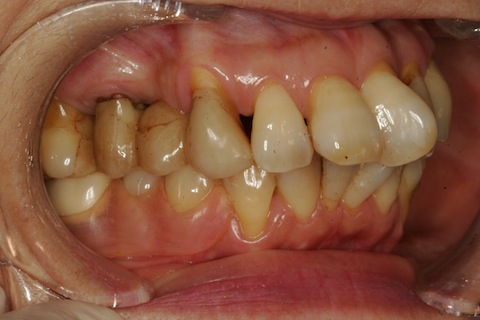

70代女性、左下56、ダツリ。残根上のブリッジw電気メスで歯肉除去CRでコア築成バイト生成wCRで連結ブリッジの形成・印象

70代女性、左下56、残根上のブリッジ。この時のつづきで、http://plaza.rakuten.co.jp/mabo400dc/diary/201510260000/口腔内にセットする前、セットしたところです。さて、どうなりますかね?壊れたときにご報告予定。